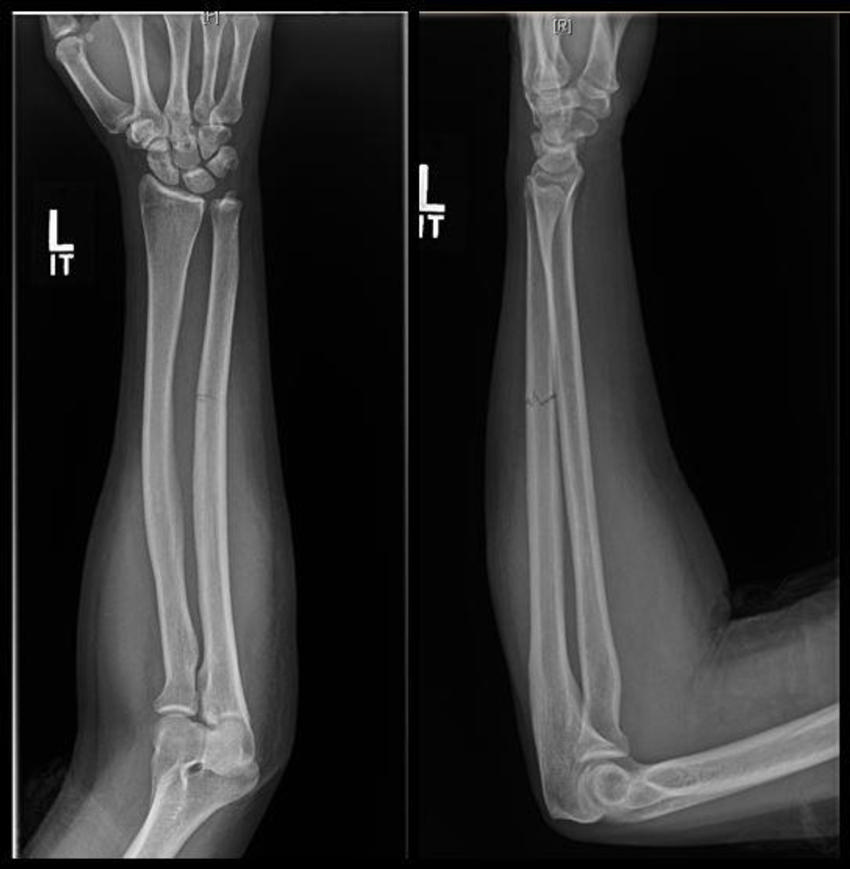

Figure 1. X-ray shows fracture to the ulna bone of the forearm.

Fractures to the ulna, the bone on the pinkie side of the forearm, often occur when people hold up their hands to protect their faces from being struck with an object. These breaks are referred to as “nightstick fractures,” because they are frequently seen in people who try to block blows from nightsticks wielded by police officers.

Analysis of the radiographs demonstrated that intimate partner violence was strongly associated with minimally displaced fractures.

“The radiological characteristics we were looking at were the location of the fracture, the pattern of the fracture in terms of how it broke, and the displacement of the fracture,” said study lead author David Sing, M.D., an orthopedic surgery resident at Boston Medical Center. “Out of all those things, what we usually saw was a minimally displaced fracture, meaning the bone is broken all the way through but has not shifted significantly.”